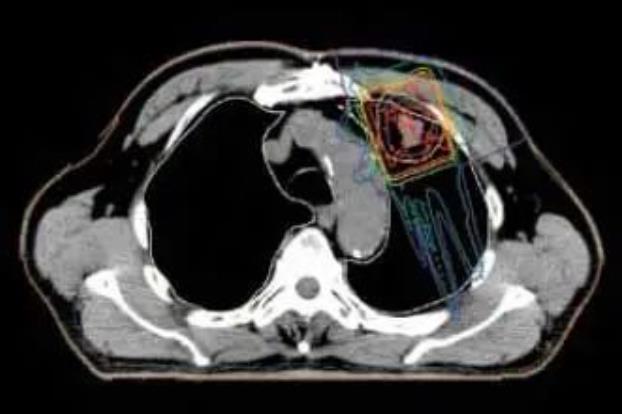

肺癌根據癌細胞的形態可以分多種類型。對于病灶局限于肺部的肺癌,根據病灶的位置,最短的治療時間約為2周(門診治療)。對于有附近淋巴結轉移的晚期非小細胞肺癌,通常需要聯合化療進行6~7周的質子治療。每次治療大約20分鐘,對病灶的照射時間只有2~3分鐘。

與傳統的放射治療相比,質子治療減少了對肺部和心臟、骨髓等器官的輻射量,并降低了治療的副作用。

質子治療可以減少對周圍正常肺組織的照射劑量,只對病變部位進行集中照射。

在開發各種新型抗癌藥物和分子靶向藥物的同時,人們也在嘗試通過增加放射劑量來提高治療的效果。雖然增加放射劑量對周圍正常肺部的影響令人擔憂,但質子療法有可能在不增加副作用的情況下增加照射劑量。今后,人們還會利用質子療法進行放射治療劑量增加試驗,以便在確認安全性的同時提高治療效果。